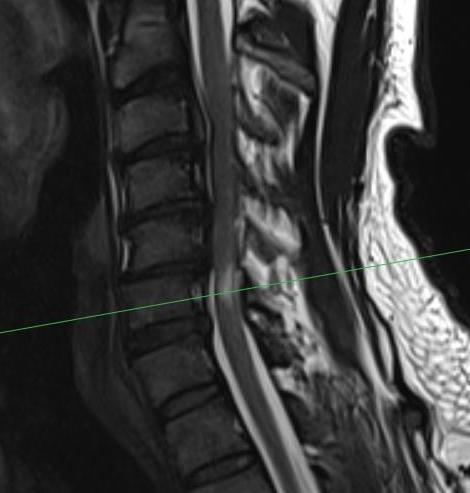

MRI

1. Space available for cord (SAC)

- Sagittal diameter of spinal canal - sagittal diameter spinal cord

- normal (17mm)

- relative (13mm)

- absolute stenosis (10mm)

Reduced by disc / osteophytes / OPLL / deformity / instability

Single level stenosis Double level stenosis Multi-level stenosis

2. Compression Ratio

- banana cord

- divide the smallest AP diameter by largest transverse diameter at same level of spinal cord

- ratio of < 0.4 after decompression particularly with myelopathy > 6 months has poor prognosis

Banana shaped cord

3. Cross sectional area of spinal cord

- < 30 mm2 poor prognosis

4. Evidence of cord edema / spinal cord damage

- often seen after acute injury in setting of stenosis

- best seen on STIR MRI

Spinal cord edema / injury

MRI and CT in same patient with OPLL